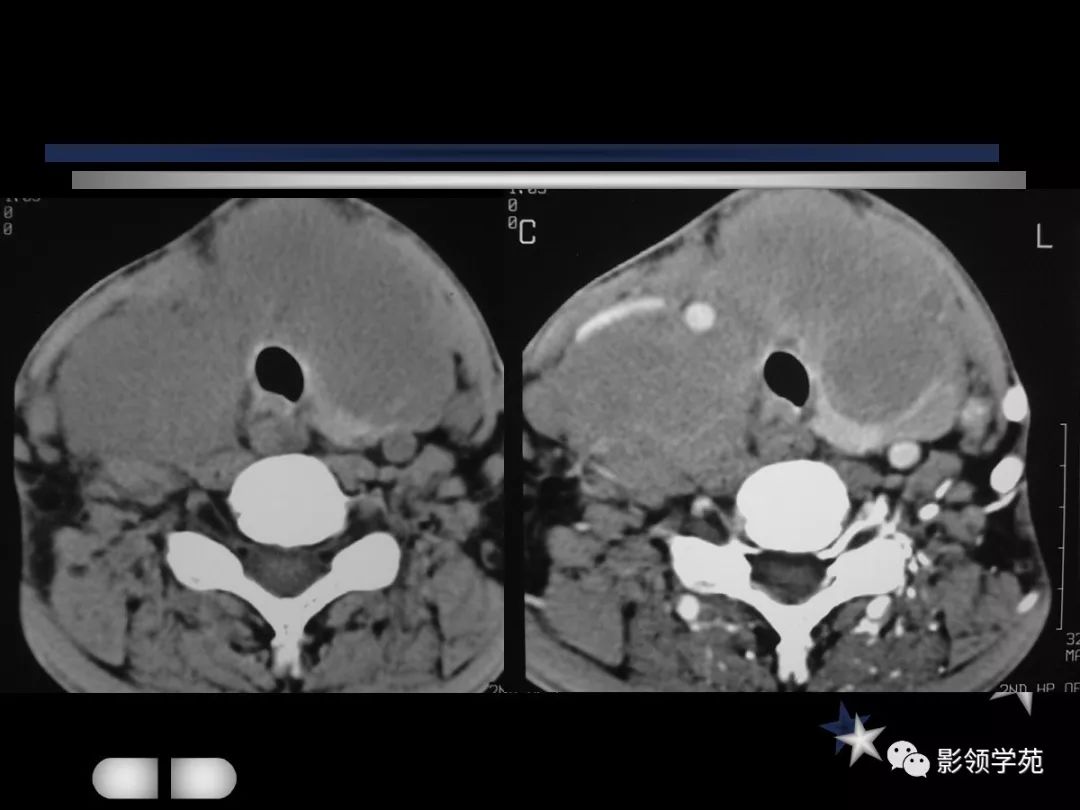

颈部常见疾病影像诊断

- 颈动脉体瘤

- 淋巴结肿大性疾病